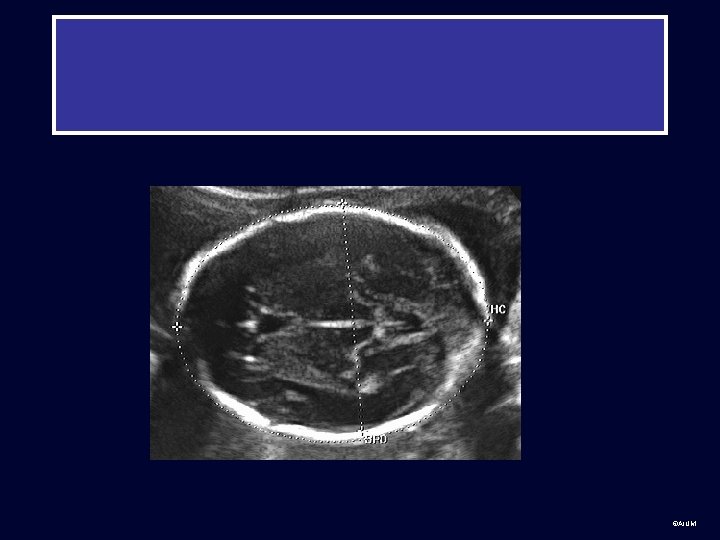

Second Trimester • After 13 -14 weeks, measurements used for dating are: biparietal diameter (BPD), head circumference (HC), abdominal circumference (AC), and femur length (FL) ©AIUM

Fetal dating: HC head circumference Note: HC measured on the outside ©AIUM